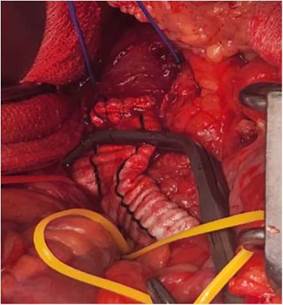

Figura 2: Aneurisma iliaco izquierdo en el tranquirúrgico, vemos en la primera imagen integro y en la segunda evidenciamos el contenido. Autoría propia.

Se presenta el caso de un paciente masculino de 75 años de edad, que acude al servicio de emergencias del Hospital obrero N°2 de la Caja nacional de Salud, Cochabamba, con un cuadro clínico de más o menos 3 semanas de evolución, caracterizado por presentar dolor lumbar de inicio súbito, secundario a realizar esfuerzos grandes, debilidad en miembros inferiores, astenia, adinamia y mareos. Antecedentes: Insuficiencia cardiaca, enfermedad de Chagas, bloqueo auriculoventricular grado 3 y portador de marcapasos hace 20 años. Al examen físico regular estado general, consciente, orientado, afebril, hemodinámicamente estable, al examen físico regional sin particularidades. Laboratorios dentro de parámetros normales. Se le realiza exámenes complementarios: Ecografía abdominal que reporta un aneurisma fusiforme de la arteria iliaca común izquierda, trombosis mural aneurismática de evolución subaguda, que compromete el 50% de la luz aproximadamente y una tomografía Abdominal con contraste donde se evidencia aneurisma bi-iliaco, con diámetros de arteria iliaca izquierda (64 mm) y derecha (35 mm), que se extiende la bifurcación de la iliaca sin datos de disección ni sangrado. Paciente es transferido al servicio de Cirugía, donde se le propone cirugía y el paciente acepta. Se le realiza como tratamiento quirúrgico una derivación aorto-bifemoral con una prótesis de dacrón, por un abordaje transabdominal. Pasa a salas de terapia intensiva, donde como tratamiento médico se le da soporte con fluidoterapia, analgésicos, profilaxis antibiótica y anticoagulación, evolucionando favorablemente. El décimo segundo día postoperatorio se realiza ecografía de control, donde se evidencia permeabilidad de la prótesis, pasando a salas generales. Es dado de alta el décimo quinto día postoperatorio.

En nuestro caso se optó por una cirugía abierta por los diámetros de los aneurismas, ya que era bilateral se escogió un abordaje transperitoneal y no retroperitoneal, ya que el mismo facilita la visualización y el procedimiento. Se requirió de un cirujano cardiovascular, cirujano vascular periférico y cirujano general. Encontramos actualmente un reporte de caso en Madrid-España del año 2025, donde a pesar de tener diámetros mayores a 3.5cm en los aneurismas aorto bi-iliaco, ya se está optando por tratamientos netamente endovasculares complejos exitosos4,9. Que difiere de lo publicado en el 2020 en la Revista Médica del Instituto Mexicano del Seguro Social, donde reportan que los tratados de forma endovascular como complicaciones presentaron claudicación, isquemia colónica e isquemia de médula espinal. Además, que a comparación de la cirugía abierta presentaron mayor probabilidad de oclusión o fuga, por lo cual la cirugía abierta sigue siendo buena opción, y fue la que escogimos en nuestro paciente5.